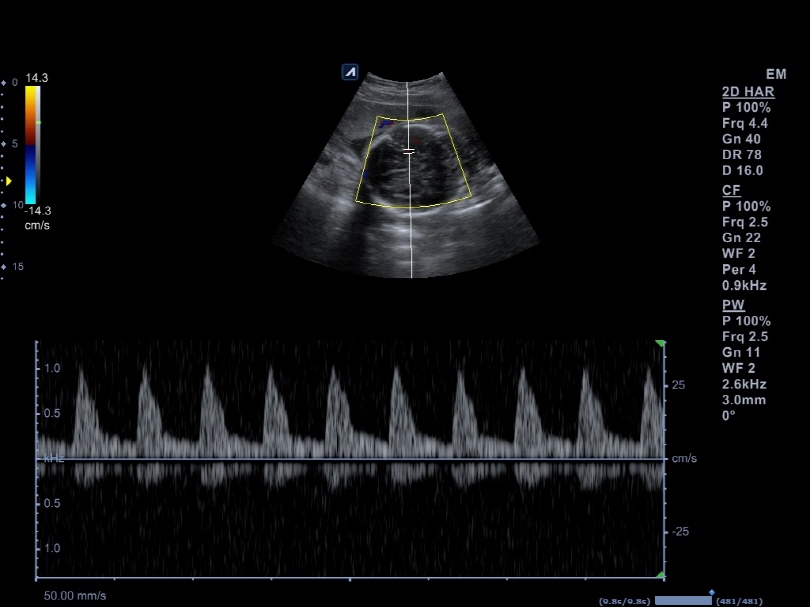

P1-5CT

Single crystal phased array transducer (1-5MHz)

Application:

Abdomen, Cardiac, EM, TCD

SP3-8T

Phased array transducer (3-8MHz)

Application:

Abdomen, Cardiac, EM, Pediatric